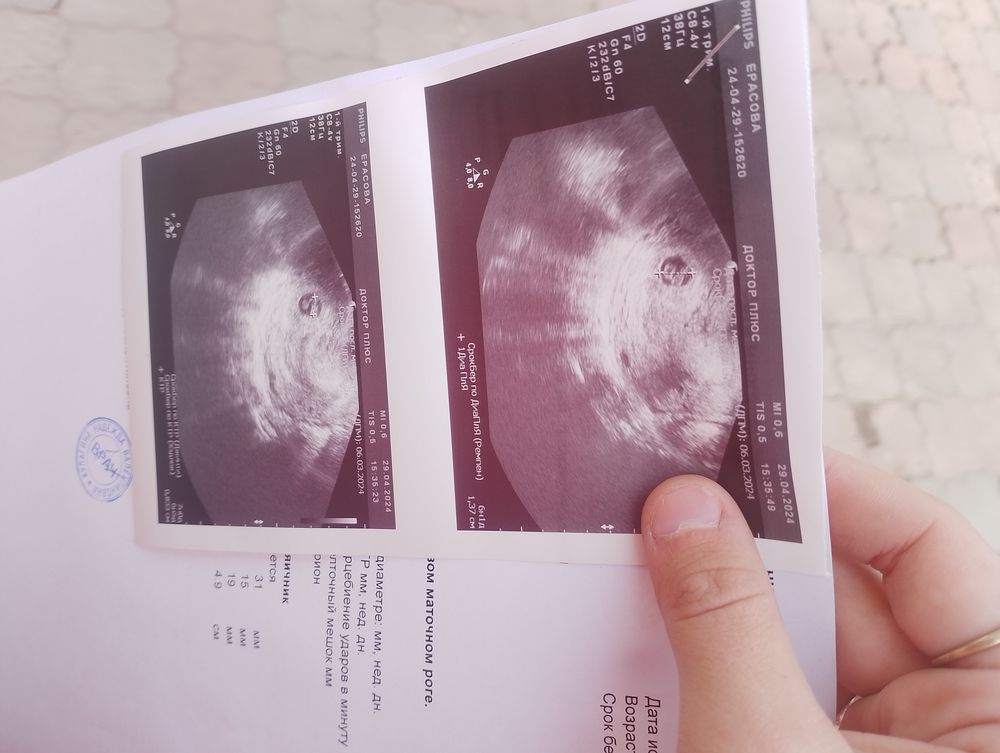

Девочки, эмбрион растёт, а плодное яйцо нет.

Девочки, эмбрион растёт, а плодное яйцо нет.

У вас все еще сохраняется 5 мм между КТР и ПЯ. Это та самая минимальная разницы. Может разогнаться. Только ждать, пока что не понятно и никто не даст точных прогнозов.